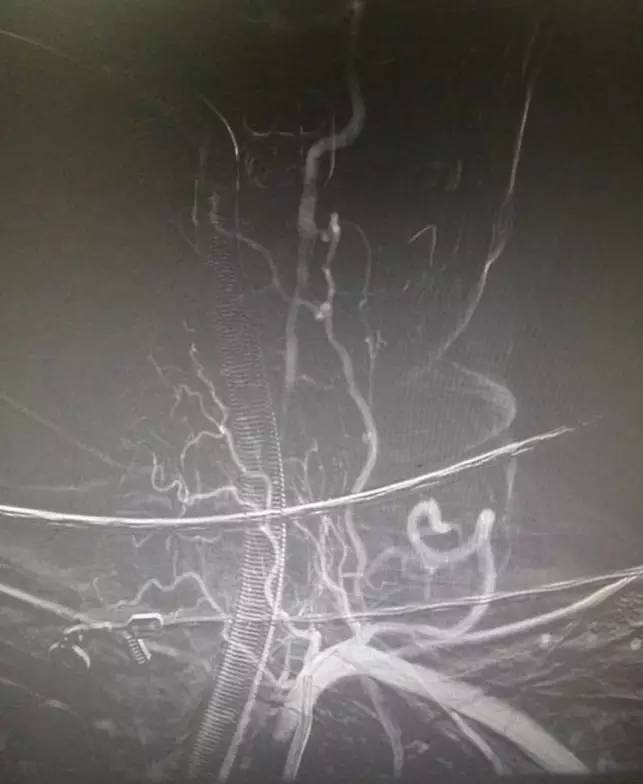

▼术后复查头颅MRI显示小脑蚓部及小脑半球有散在的梗死灶,脑干未见梗死。头颅MRA显示后循环血管通畅。